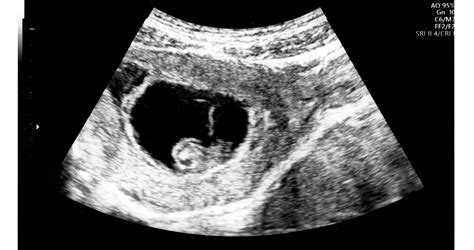

Az elölfekvő méhlepény diagnosztizálása: A klinikai kép alapján már valószínűsíthető a rendellenes elhelyezkedés, és hasi ultrahangvizsgálattal a lepény helyzete meghatározható és követhető. (Hüvelyi ultrahangot ilyen esetben általában nem végezhetnek, vagy csak nagyon indokolt esetben.) Az elölfekvő méhlepény diagnosztizálását segítik a terhesség során kötelezően elvégzett ultrahangvizsgálatok.

A placenta praevia a hasi ultrahangon jól látszik, az orvos könnyen észleli, hogy a méhlepény rendellenes helyen tapad. Placenta praevia esetén a kismamák veszélyeztetett terhesnek számítanak. A placenta praeviának különböző fokozatai vannak. Megesik, hogy a belső méhszáj területét teljes egészében fedi a lepényszövet, de előfordul, hogy csak részben. Olyan típusa is van a rendellenességnek, amikor a lepény csak eléri a belső méhszájat, illetve olyan is, amikor ugyan megközelíti azt, de a szélét nem éri el.